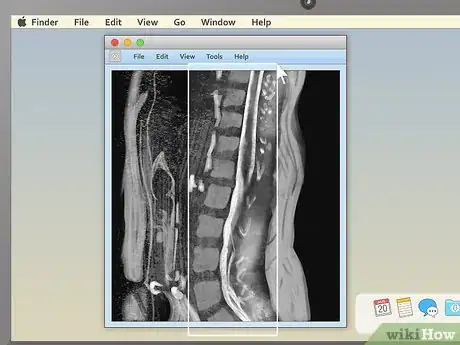

2Examine the structure of the vertebrae for spinal MRIs. MRIs of the spine are typically some of the easiest for non-doctors to read (especially in sagittal view). Look for noticeable misalignments in the vertebrae or fluid discs. Having just one of either be out of alignment (as in the example above) can be the source of serious pain.

- Behind the spinal vertebrae, in sagittal view, you'll see a white, rope-like structure. This is the spinal cord, the structure connected to all the body's nerves. Look for spots where the vertebrae or discs seem to "pinch" or press into the spinal cord — because the nerves are so sensitive, just a little pressure can lead to pain.